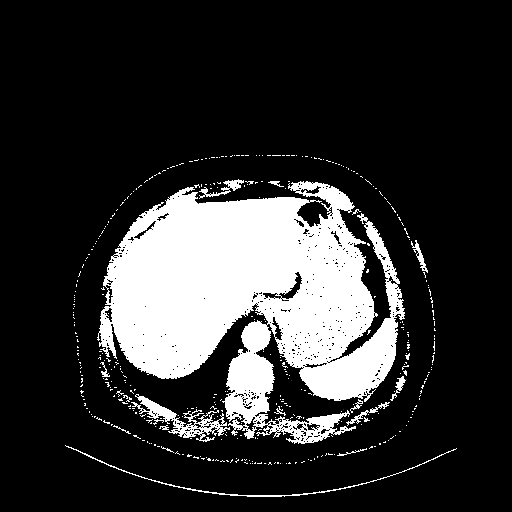

Reconstructed NATIVE CT scan (cycle consistency)

Full window (WL 1023.5, WW 4095 β†’ Low βˆ’1024, High +3071)

Actual HU range: [-1024.0, 3071.0]